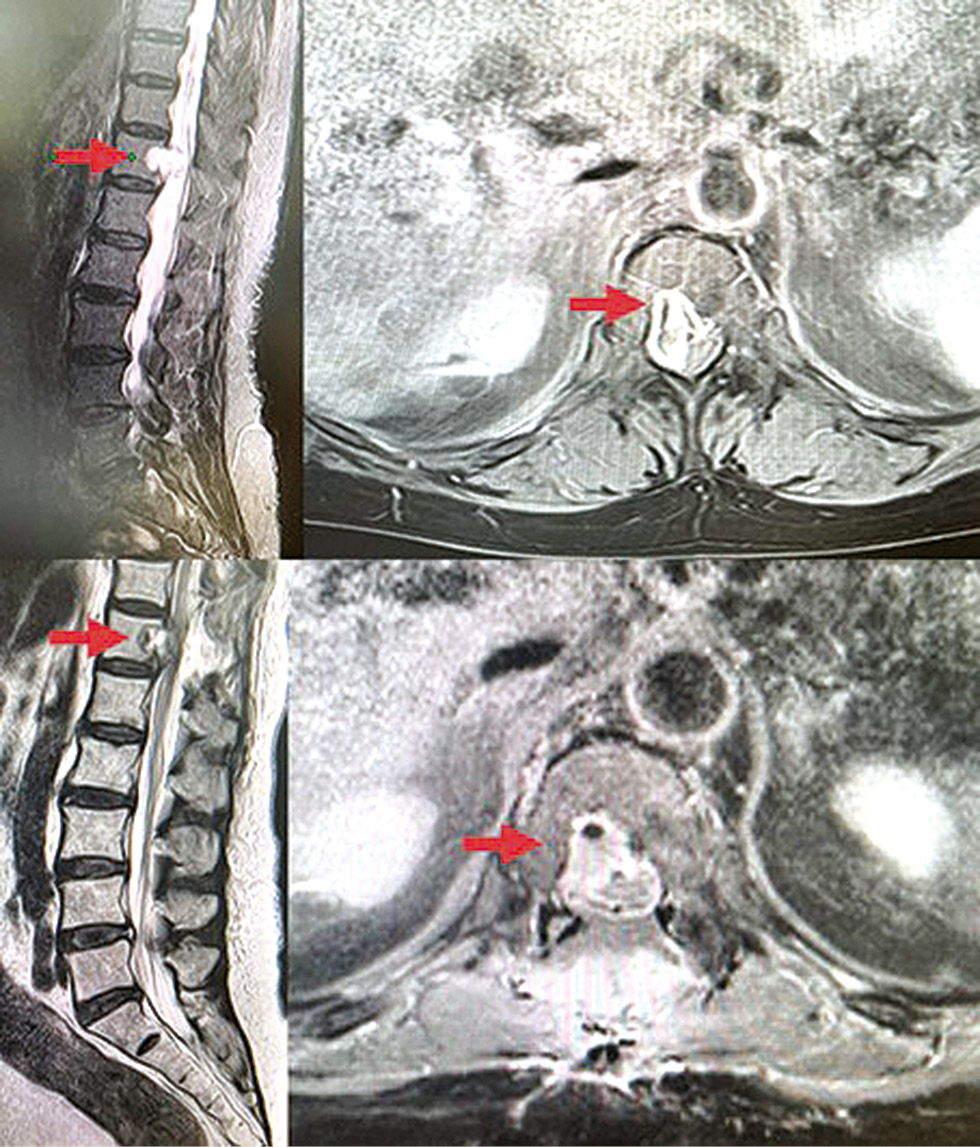

Clinical findings from November 2022 to January 2023 showed negative changes: worsening of lower paraparesis (from mild to moderate). Subjective complaints included right side back pain radiating to the right leg (pain intensity on a visual analogue scale: 70%–80%), sleep for no more than 2–3 h due to therapy with nonsteroidal anti-inflammatory drugs, weakness, decreased appetite, and tingling in the legs. The patient had difficulty walking and required the assistance of family members. MRI findings two months after surgery (January 2023): a tumor measuring 1.6×1.1 cm along the posterior surface of the Th12 vertebral body, extending to the spinal canal and compressing the adjacent spinal cord segment. Contrast-enhanced MRI revealed a weak, heterogeneous increase in MR signal of the tumor (most likely, residual tumor) (Fig. 2).

Fig. 2. MRI of the spine 2 months after surgery, T1 mode (residual tumor in Th12).

Рис. 2. МРТ позвоночника через 2 мес. после операции, режим T1 (остаточная опухоль в Th12).

In late March 2023, the patient was admitted to a daytime radiotherapy center. A follow-up MRI revealed a tumor measuring 1.5×1.2 cm along the posterior surface of the Th12 vertebral body, extending to the spinal canal, with no signs of spinal cord compression (Fig. 2). Subjective complaints included weakness in the right leg, discomfort in soft tissues of the abdomen and back on the right, tingling in the right leg, pain in the right leg, weakness, and fatigue. The patient had difficulty walking and required the assistance of family members. The patient received tramadol, an opioid analgesic, at a dose of up to 400 mg/day.